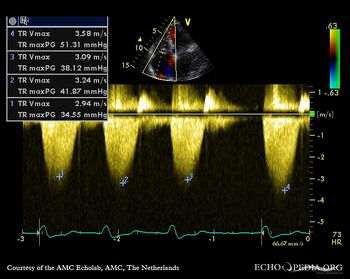

Continuous-wave Doppler signal of tricuspid regurgitation, pulmonary hypertension A4CH: dilated coronary sinus